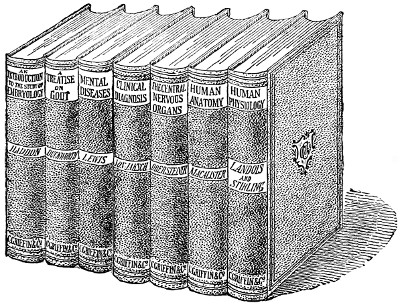

| Williams’ Apparatus for Investigating Action of Poisons on the Frog’s Heart, | 44 | |